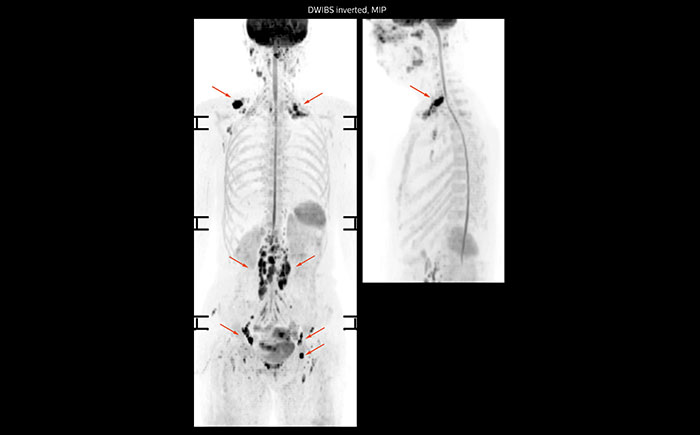

Whole body diffusion

A 61-year-old female with a malignant lymphoma underwent an MRI exam with whole body diffusion weighted imaging (DWIBS) as well as PET. On the images shown, the resolution of DWIBS is better than PET, which allows visualization of the small pelvic lesions and almost no distortion is seen in the neck area.